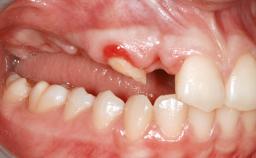

A 56-year-old woman presented for treatment with complete edentulism of the maxilla. She had been using a complete removable denture since she was relatively young (age 30). Her chief complaint at presentation was lack of retention of the upper denture and a desire for a better restoration in order to improve retention, function, and esthetics. An initial clinical examination showed that the anterior maxilla was moderately atrophic both horizontally and vertically, also revealing a vertical deficiency of the posterior alveolar process. The mandible included natural teeth from 45 to 35, with previous extrusion of the anterior teeth that was being orthodontically treated. Also, there were two external hexagon dental implants at sites 46 and 36 that had been inserted elsewhere at a previous point in time. As the conditions in the mandible were healthy, including the teeth and the two implants, the patient had no complaints there.